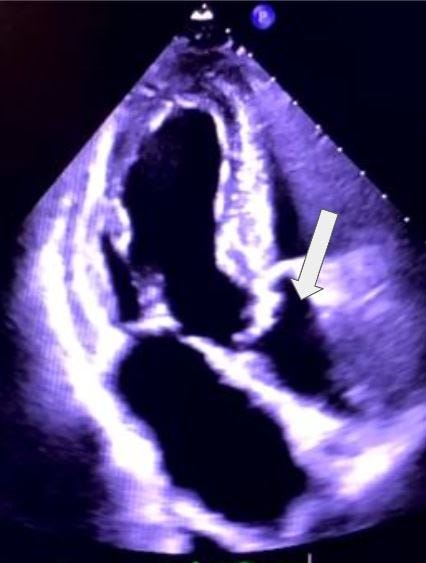

Which aortic cusp is the arrow indicating in this parasternal short axis image?

A. Anterior cusp

B. Non-Coronary cusp

C. Lateral cusp

D. Right coronary cusp